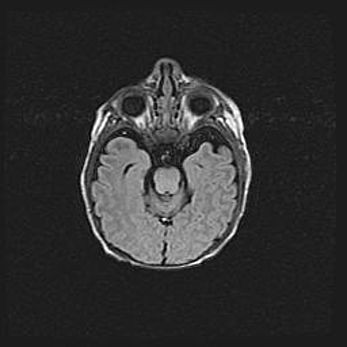

Церебральная ишемия II.

Возраст: 5 дней

Вес: 3400 г

Пол: женский

Окружность головы: 35 см

Срок гестации: 39 недель

Церебральная ишемия – это заболевание, характеризующееся недостаточностью (гипоксией) либо полным прекращением (аноксией) снабжения мозга кислородом по причине закупорки одного или нескольких сосудов. Это приводит к  что метаболическим расстройствам различной степени тяжести в тканях головного мозга, развитию коагуляционных некрозов и гибели нейронов.